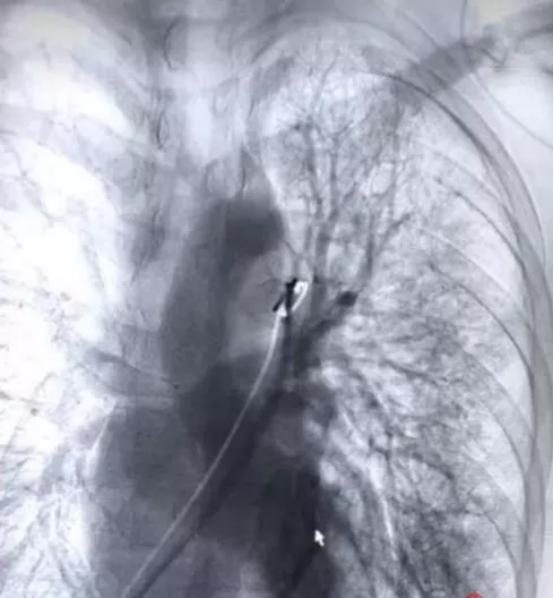

医生经检查发现,小张是支气管扩张引起的咯血,如不赶快止血极易窒息。医院迅速开通绿色通道,将他送进手术室进行血管介入治疗,用栓塞剂将破裂血管栓塞后,才停止咳血。